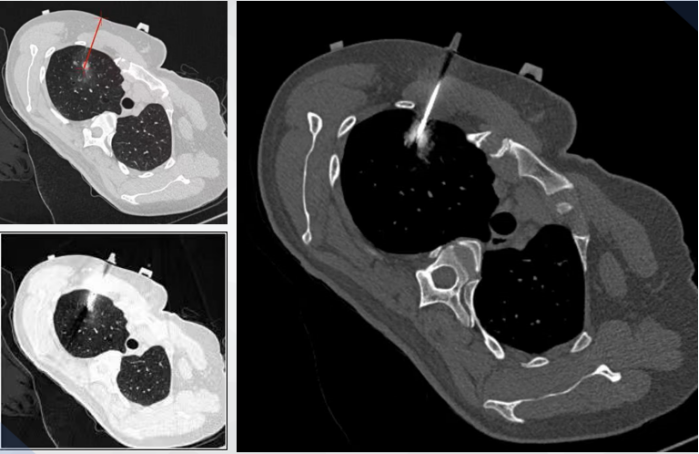

考虑到该肺结节位置的特殊性,常规的经皮CT穿刺定位和经支气管磁导航定位都存在一定局限性,而使用穿刺手术机器人,不但可以提升肺结节定位的精确度,减少并发症,还可以在肿瘤穿刺活检、消融等多个微创治疗手段中发挥机器人的优势。最后,何建行教授团队决定采用机器人辅助导航系统来明确肺结节的性质并进行相应治疗。

治疗中,团队先使用机器人辅助导航系统进行了CT引导下的穿刺活检,成功获取了病理组织标本,确诊右上肺结节为肺腺癌。

2023年3月25日,在机器人辅助导航系统的协助下,团队的崔飞主任在放射科为患者成功完成了射频消融术。借助机器人辅助导航系统的精准定位功能,确保了电极毫无偏差地精确插入肺结节中。整个射频消融术过程,患者包括血压、血氧饱和度和心率的生命体征,始终保持稳定状态。术后,团队进行了定期CT随访观察,至今未发现任何气胸、严重咯血或胸腔积液等不良反应。